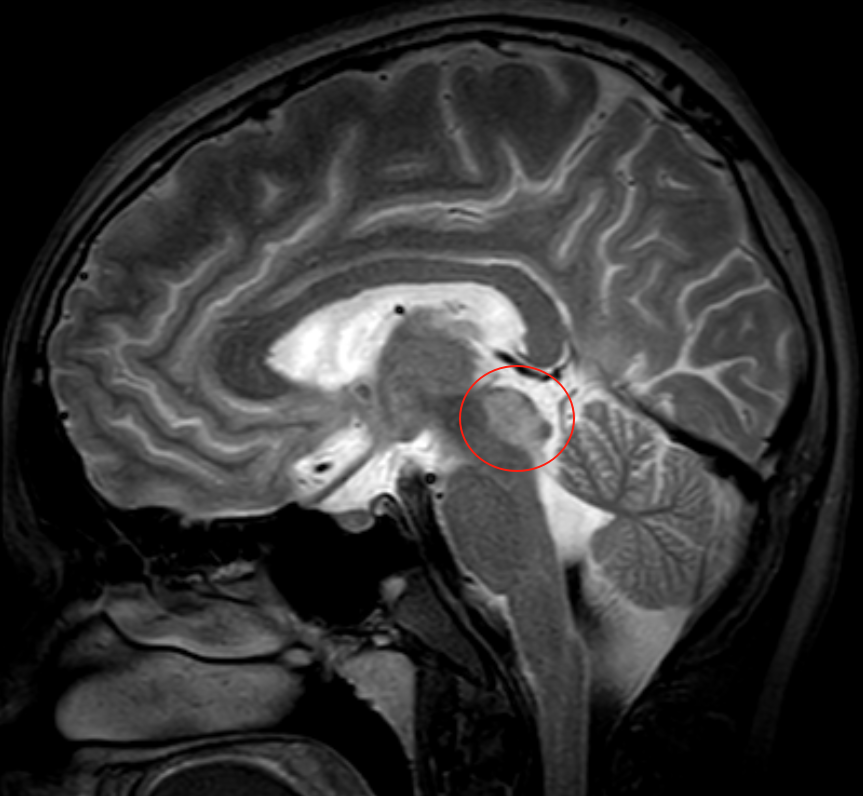

中脑背侧、顶盖部占位性病变,父母为17岁少年全力托举

17岁少年2年前因脑积水行分流术,症状一度缓解。4个月前头痛复发伴视物重影,调整分流压力无效。近1月病情进展,出现眼球运动障碍、吞咽困难及嗜睡,影像学显示中脑背侧、顶盖部占位,约19*16*11mm,疑似胶质瘤。面对不断加重的病情,患者父母带着希望寻求巴教授的帮助。

巴教授的策略是不同的,”我会尽量切除肿瘤的绝大部分,这样我们也能拿到足够大的标本,有助于做出精确的诊断。术后不到6周,孩子可能回归校园、正常生活……“